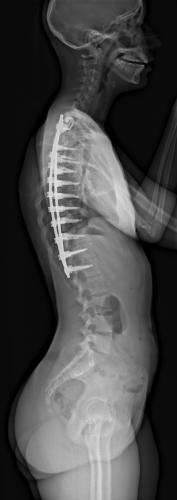

Images de scolioses opérées 16 janvier 202418 janvier 2023 par Damien Scoliose Thoracique 1 Radiographie pré-opératoire de Face Radiographie pré-opératoire de Profil Radiographie de Face à 3 mois post-opératoire Radiographie de Profil à 3 mois post-opératoire